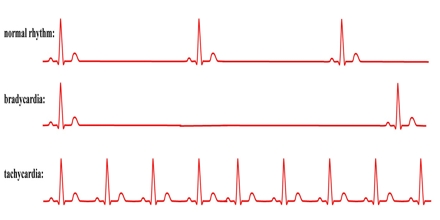

Causes and risk factors of cardiac arrhythmias. New study uncovers major cause of deadly heart arrhythmias. Averting deadly arrhythmias